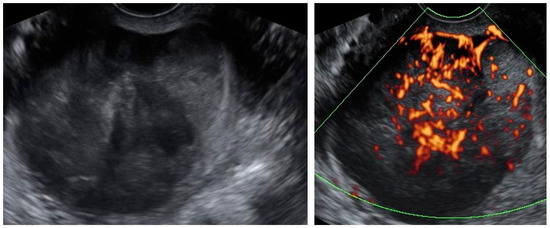

| Case Number (Age, Years Old) | Ultrasound Diagnosis of Uterine Lesion | Figure | Initial Treatment/ Histological Diagnosis Required (Doctor’s Decision) | Initial Patient’s Willingness to Undergo Surgery for the Uterine Lesion | Histology from Core Needle Biopsy | Patient Decision to Undergo Surgery for the Uterine Lesion | Histology from Definitive Surgery | Did Core Needle Biopsy Provided Additional Information to Ultrasound | Did Core Needle Biopsy Provided Useful Information for the Clinical Management |

|---|---|---|---|---|---|---|---|---|---|

| 6 (38) | Atypical uterine lesion | Figure A6 | Yes | No | Leiomyoma, epithelioid variant (UG-TUC core needle biopsy) | Yes (lesion enlarged during follow-up) | Leiomyoma, epithelioid variant | Yes | Yes |

| 7 (29) | Atypical uterine lesion | Figure A7 | Yes | Yes | Leiomyoma (UG-TUC core needle biopsy) | Yes | Leiomyoma with signs of degenerations | Yes | Yes |